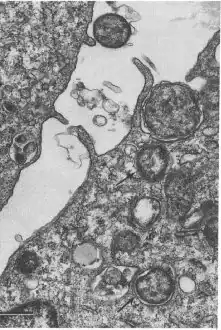

Ehrlichiosis is a tick-borne[3] bacterial infection,[4] caused by bacteria of the family Anaplasmataceae, genera Ehrlichia and Anaplasma. These obligate intracellular bacteria infect and kill white blood cells.

Ehrlichia species are transported between cells through the host-cell filopodia during the initial stages of infection; whereas, in the final stages of infection, the pathogen ruptures the host cell membrane.[10]